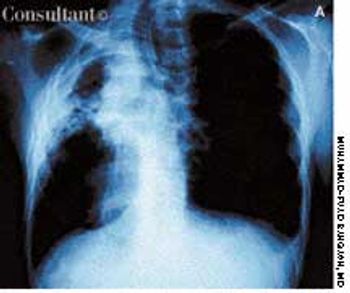

A 13-year-old girl who had leukemia presented to the emergency department with fever; chills; weight loss; fatigue; and a painful, erythematous rash with a central black lesion on the upper thigh. The patient was neutropenic and had been undergoing chemotherapy for 1 week.